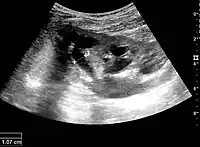

Figure 19. Centrally-located stone with posterior shadowing. No hydronephrosis is present. Measurement of kidney length on the US image is illustrated by ‘+’ and a dashed line.[1]

With US, larger stones (>5–7 mm) within the kidney, i.e., in the calyces, the pelvis and the pyeloureteric junction, can be differentiated, especially in the cases with accompanying hydronephrosis (Figure 18 and Figure 19). Hyperechoic stones are seen with accompanying posterior shadowing. Additional twinkling artifacts below the stone can often be seen using Doppler US. Large stones filling the entire collecting system are called coral stones or staghorn calculi and are easily visualized with US (Figure 20). Stones in the ureters are usually not visualized with US due to the air-filled intestines obscuring the insonation window. However, ureteral stones near the ostium can be visualized with a scan position over the bladder. An exam of the ureteric orifices and the excretion of urine to the bladder can be performed by inspecting the ureteric jets in the bladder with color Doppler US.